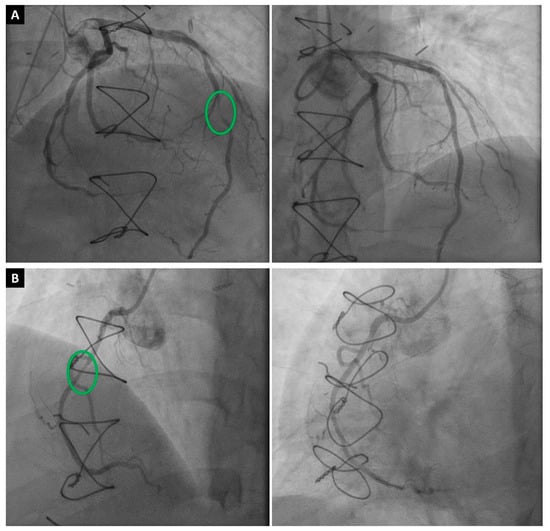

3.2.2. Cardiac Magnetic Resonance

Cardiac magnetic resonance imaging (CMR) is a non-invasive imaging modality that can provide comprehensive information about the structure and function of the heart that is relevant for the diagnosis and prognosis of CAV (Figure 3) [8]. CMR can provide information about structural changes by measuring parameters such as extracellular volume (ECV) fraction, fibrosis, and edema [58]. However, functional parameters such as myocardial perfusion reserve (MPR), diastolic strain (DS) rate by CMR, and peak filling rate (PFR) carry more importance for CAV diagnosis, as most studies using CMR have focused on MPI and strain imaging [59,60]. Therefore, a multiparametric CMR can safely measure various parameters to detect and grade CAV by assessing the myocardial tissue and function in HTx recipients without exposing them to radiation or iodinated contrast agents [61].

Figure 3.

(A) Cardiac magnetic resonance imaging (CMR) showing clear thinning (white arrows) of the anterolateral, inferolateral, and inferior mid-cavity, with subendocardial delayed enhancement in these regions suggesting a vascular etiology. The hypertrophy of the septum is profound but is presumably compensatory due to the extensive loss of lateral wall myocardium. While this CMR finding could be multifactorial, invasive coronary angiography showed a severe obstruction (white arrow) in the proximal circumflex artery (B).